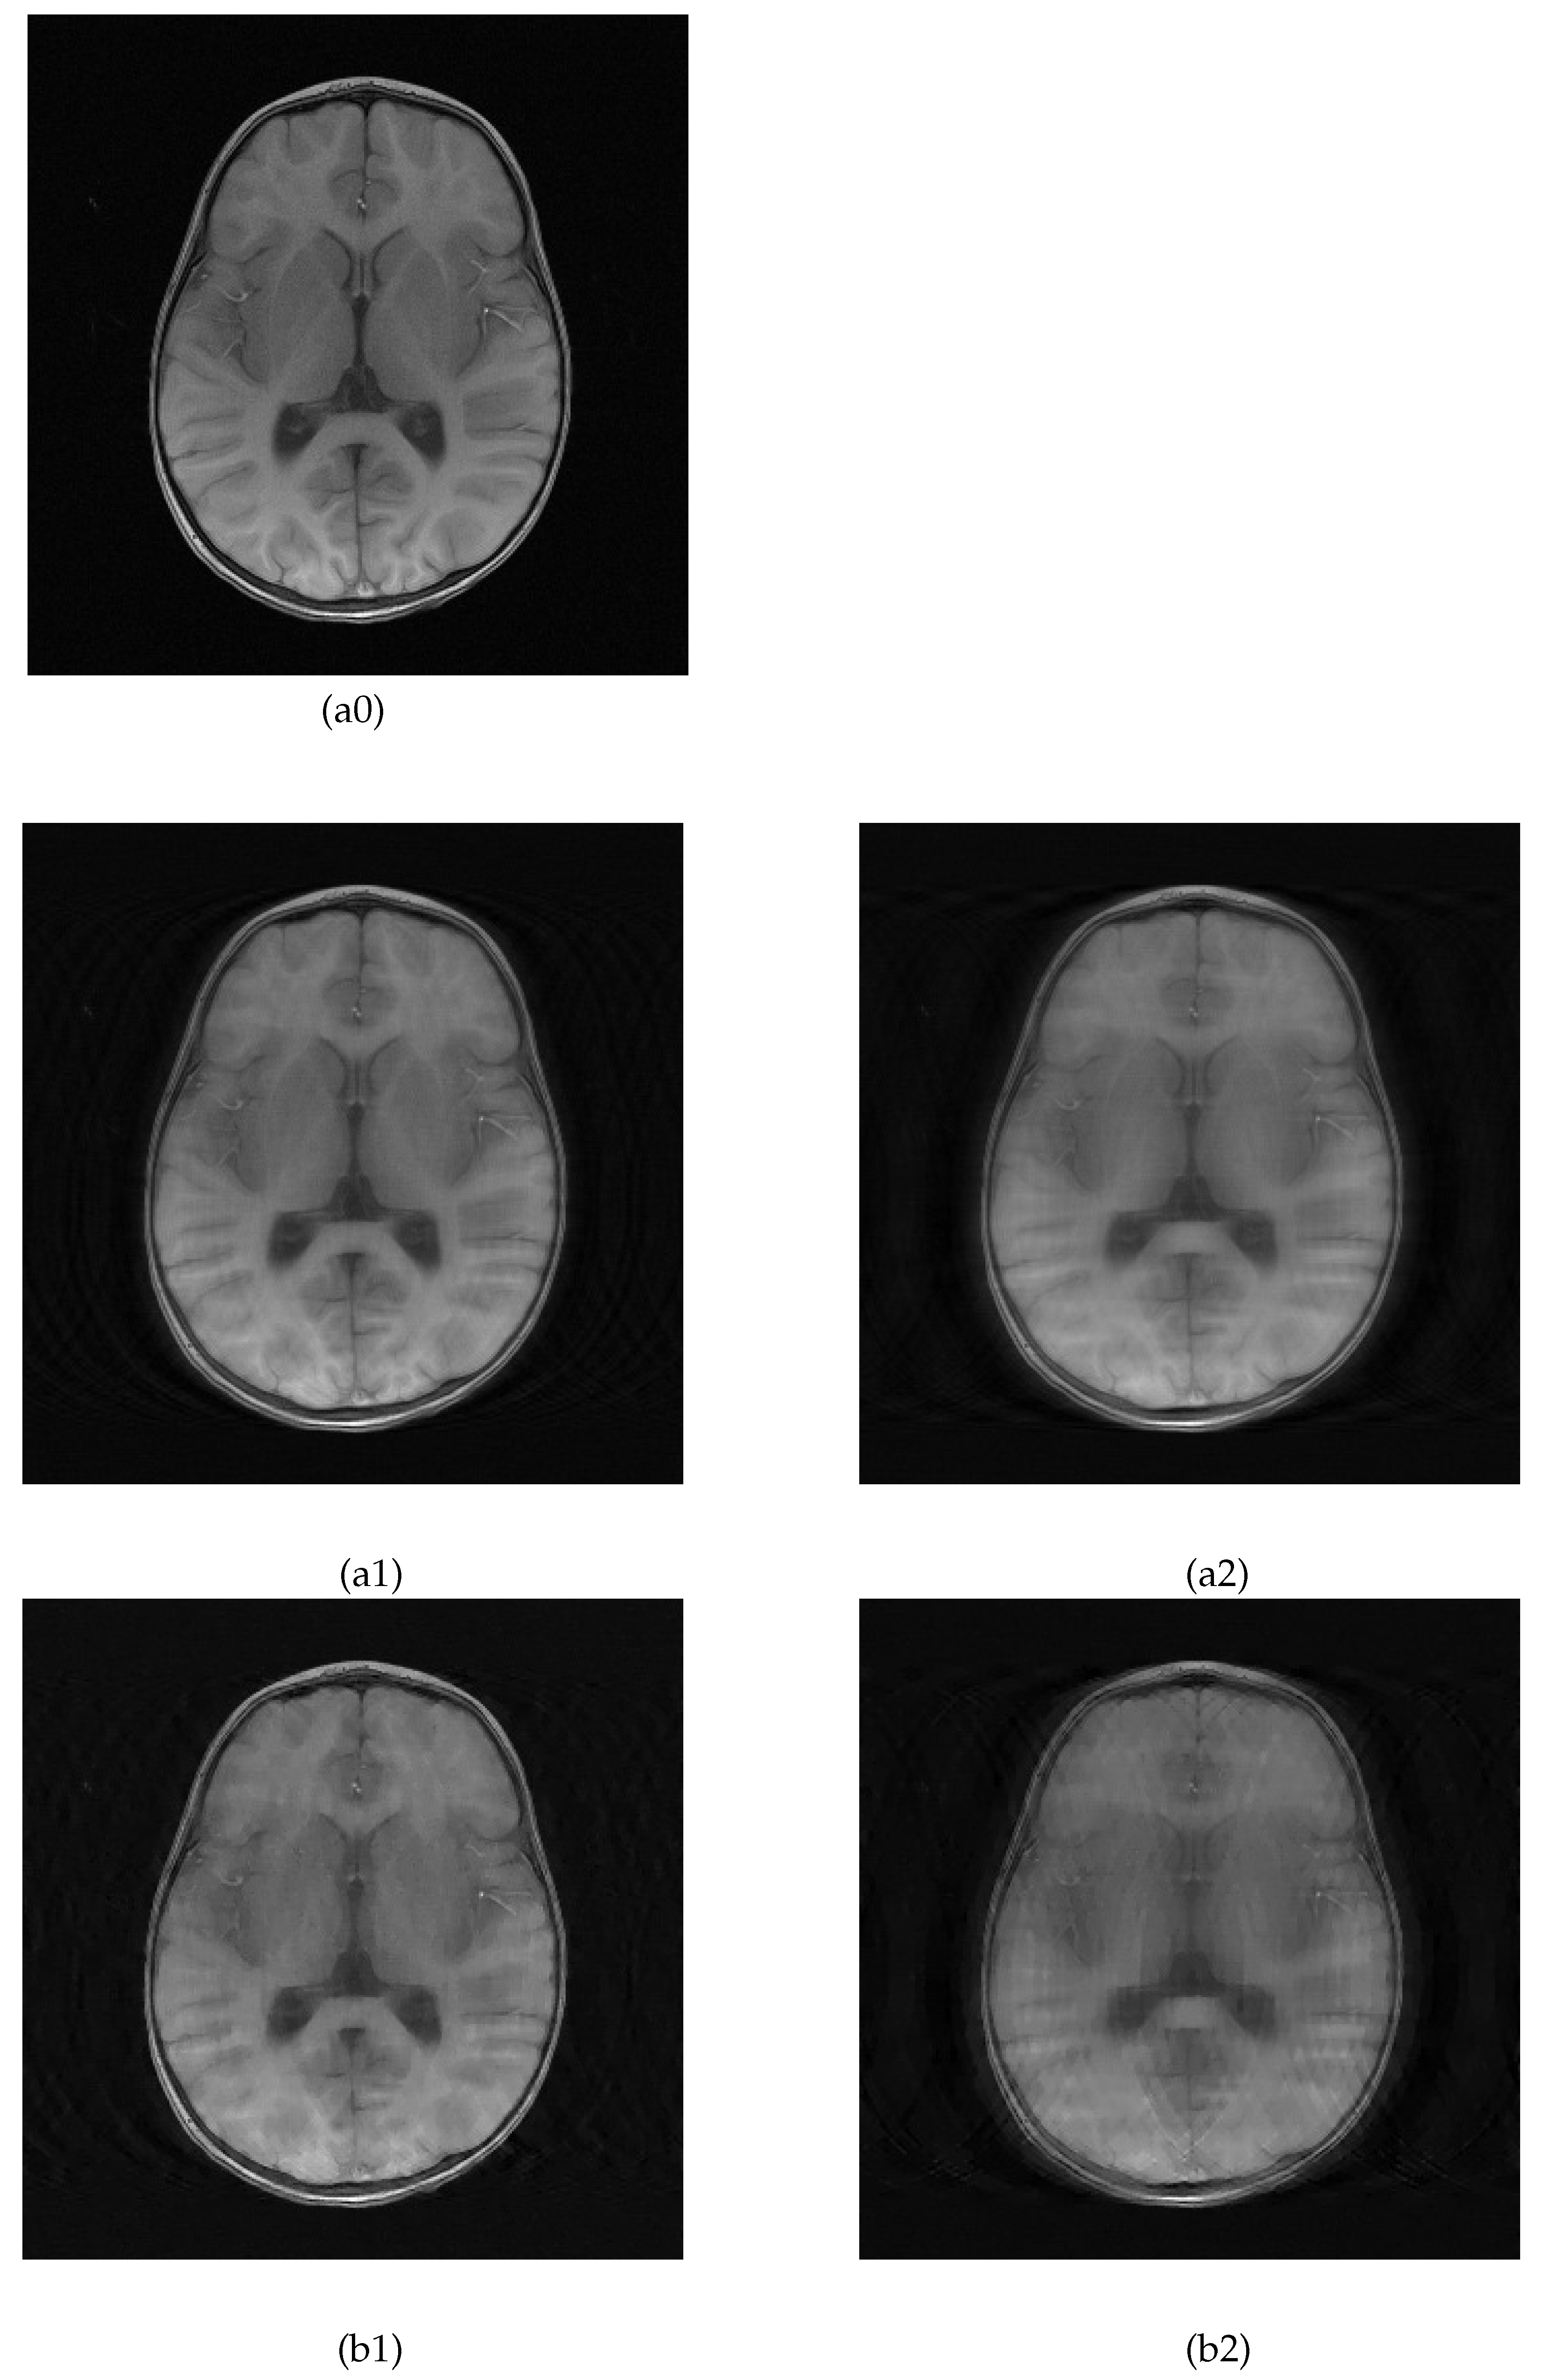

5.2. MRI Image Recovery

| Proposed | TV Method | |||||||

|---|---|---|---|---|---|---|---|---|

| PSNR | SSIM | PSNR | SSIM | |||||

| 4× | 8× | 4× | 8× | 4× | 8× | 4× | 8× | |

| Knee A | 28.5 | 26.4 | 0.657 | 0.570 | 28.2 | 24.5 | 0.615 | 0.538 |

| Knee B | 28.4 | 26.1 | 0.635 | 0.535 | 27.8 | 24.1 | 0.625 | 0.541 |

| Brain A | 27.7 | 24.1 | 0.642 | 0.524 | 26.7 | 22.3 | 0.637 | 0.493 |

| Brain B | 27.7 | 24.6 | 0.668 | 0.494 | 26.8 | 22.7 | 0.644 | 0.474 |